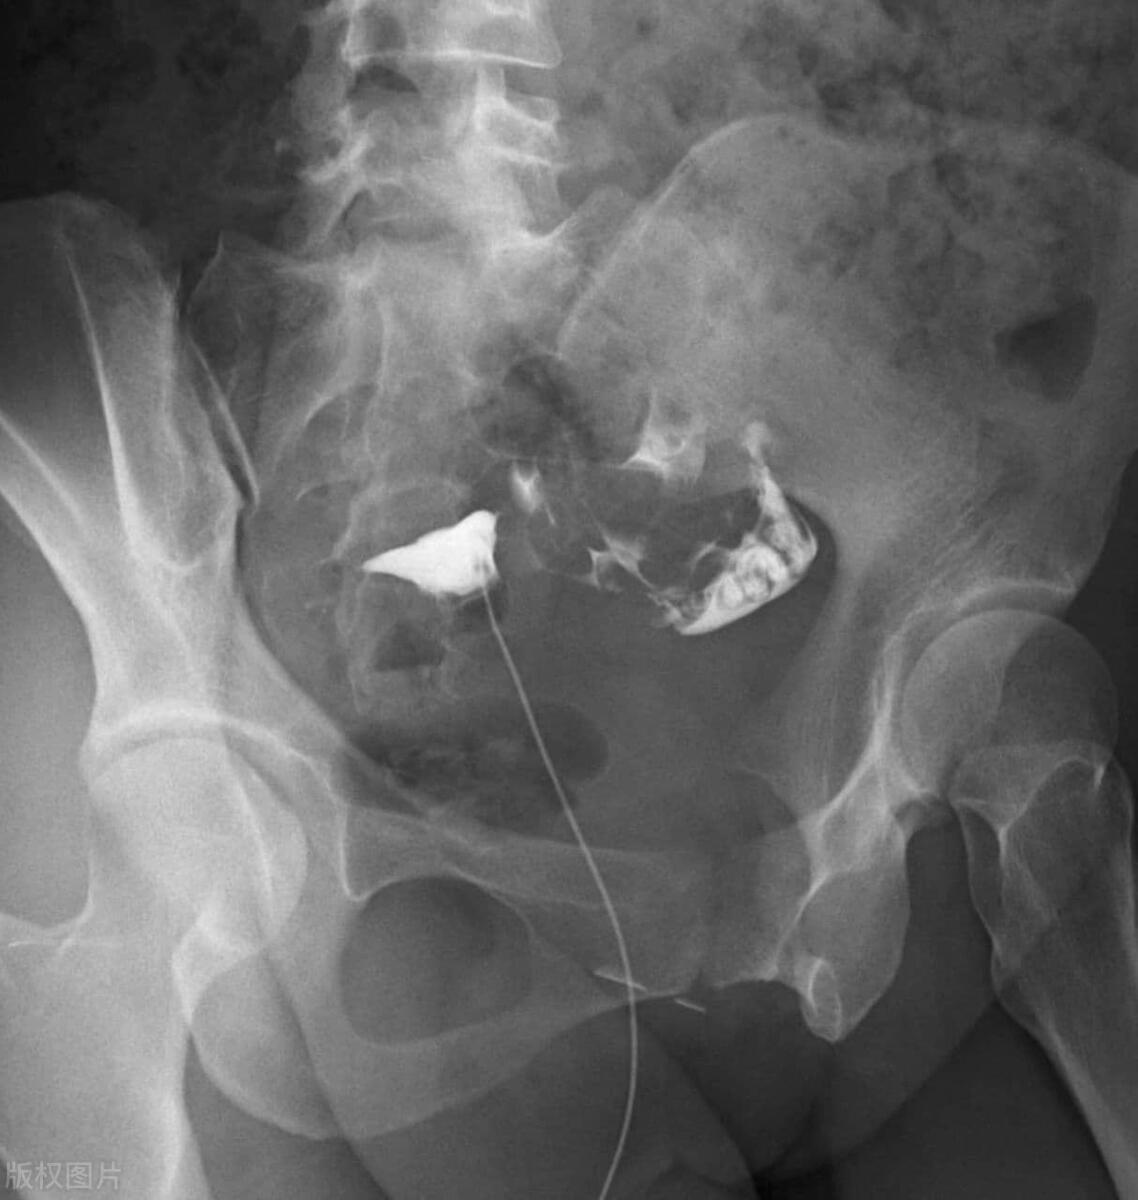

为了避免再次受孕,刘晓琳决定在医生的指导下安装避孕环,以避免再次怀孕。她认为,这是对自己和家庭最负责任的决定。

在尽量避免让家人知道这些问题的同时,刘晓琳决定去医院进行检查。她带着担忧的心情,走进了医院。经过一番基本的妇科检查,医生发现她的子宫内膜有些肿胀和发红,很可能是由于避孕环造成的炎症。

医生解释说,避孕环是一种有效的避孕方法,但是也可能导致一些副作用。在某些情况下,避孕环可能导致子宫内膜炎或其他炎症反应。这可能是由于避孕环对子宫内膜的物理刺激,或者是避孕环导致的微小创伤,让细菌有机会侵入,从而引发炎症。

除了女性结扎,还有许多其他可靠的避孕方法可供选择。例如口服避孕药、避孕环、避孕注射等。根据个体的需求和医生的建议,选择适合自己的避孕方式。